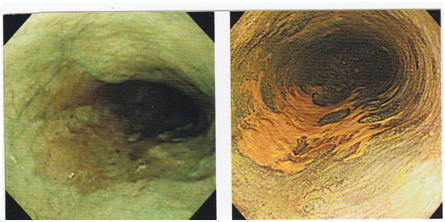

食道早期がん

図A 図B

図A:時計針で6時~10時の褐色の病変が早期癌(狭帯域光観察 Narrow Band Imaging ,NBIによる内視鏡検査)

図B:同じ症例の色素内視鏡(ヨード染色)。黄色い部位が早期癌